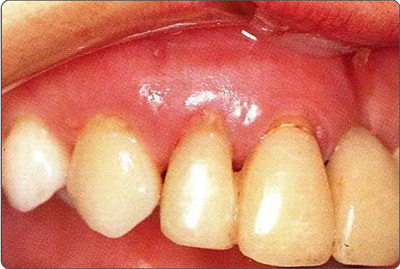

深牙周袋的治療

圖10-9  術后2周的狀態(tài)。牙齦乳頭獲得保存。較之使用GTR膜,自體骨移植更不容易引起牙齦乳頭的壞死。